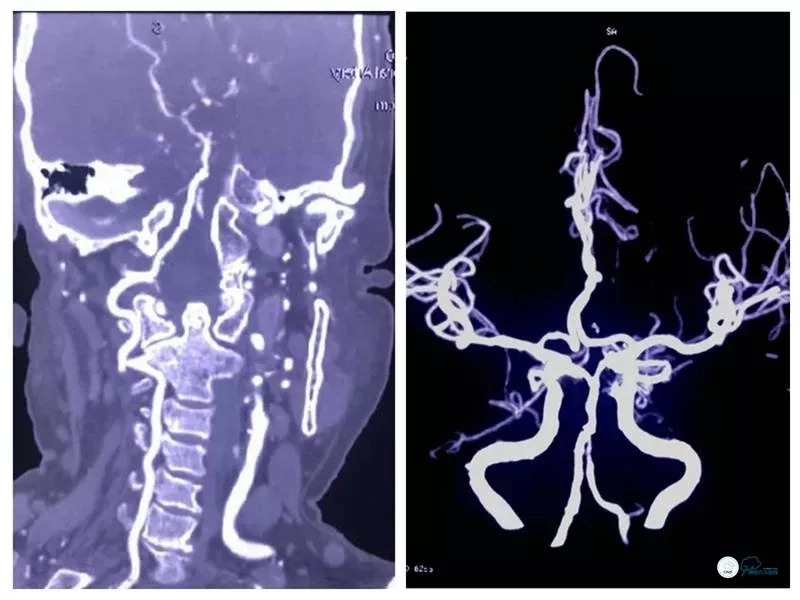

术后头颅CTA:右侧椎动脉V4段及基底动脉支架内通畅(图15)。

图15